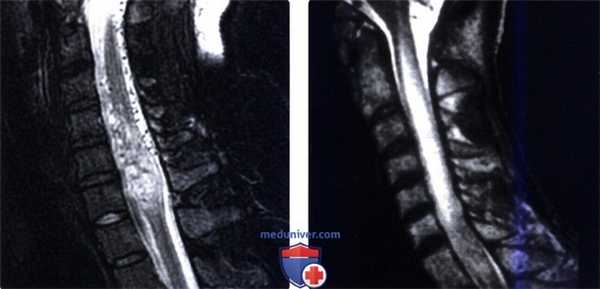

(Слева) Сагиттальный срез, Т2-ВИ FS, пациент с множественным метастатическим поражением костей, которому ранее проводилась лучевая терапия: отмечается диффузное усиление сигнала спинного мозга. Дифференциальный диагноз здесь следует проводить в первую очередь между постлучевой миелопатией и пара неопластическим синдромом.

(Справа) Аксиальный срез, Т1-ВИ с КУ, пациент с генерализованным метастатическим поражением костей: фокальное контрастное усиление сигнала центрального серого вещества спинного мозга. Подобные изменения позволяют предположить паранеопластическую миелопатию.

(Слева) Сагиттальный срез, STIR МР-И, пациент с хронической шейной миелопатией: веретеновидное гиперинтенсивное расширение спинного мозга на уровне С4-С6 с наличием множества поверхностных сосудистых полостей. Картина соответствует артериовенозной мальформации спинного мозга.

(Справа) Сагиттальный срез, Т2-ВИ, пациент с опухолью области головы и шеи в анамнезе, по поводу которой проводилась лучевая терапия: определяются признаки постлучевой миелопатии в виде диффузной гиперинтенсивности сигнала и отека спинного мозга на уровне С2-С6.